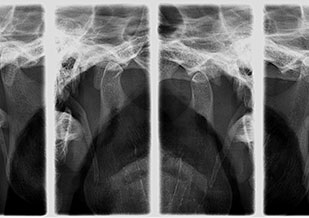

Radiografía de ATM

Es una radiografía extra oral que permite estudiar estructuras oseas de las articulaciones temporo-mandibulares en posiciones de oclusión y apertura máxima.